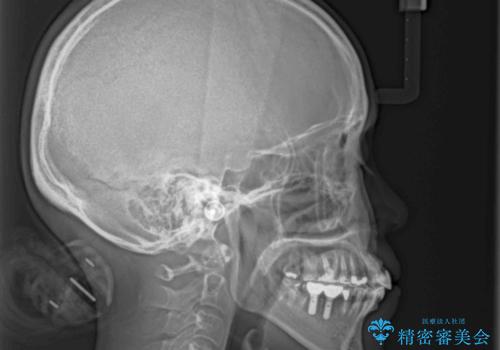

取り急ぎ下顎前歯数歯の根管治療を、銀座しらゆり歯科医院長の林先生にお願いし、それ以外に気になっている、不自然な色調のクラウン、金属部分が見えてブラッシングがしにくいインプラント補綴、口元の突出感、出血のしやすい歯周ポケットなど、全てを解決するための治療を行うこととしました。

期間と費用はかかりましたが、気になっていた部分全てを改善でき、患者様には大変満足していただきました。